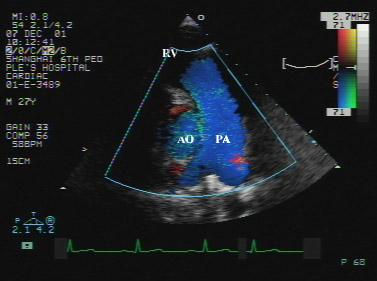

正常超声心动图

正常超声心动图,超声心动图正常值

(m型超声心动图左室短轴切面显示心肌收缩运动较正常稍有增强)

心脏解剖及正常超声心动图2008ppt

正常超声心动图-超声诊断学

超声心动图